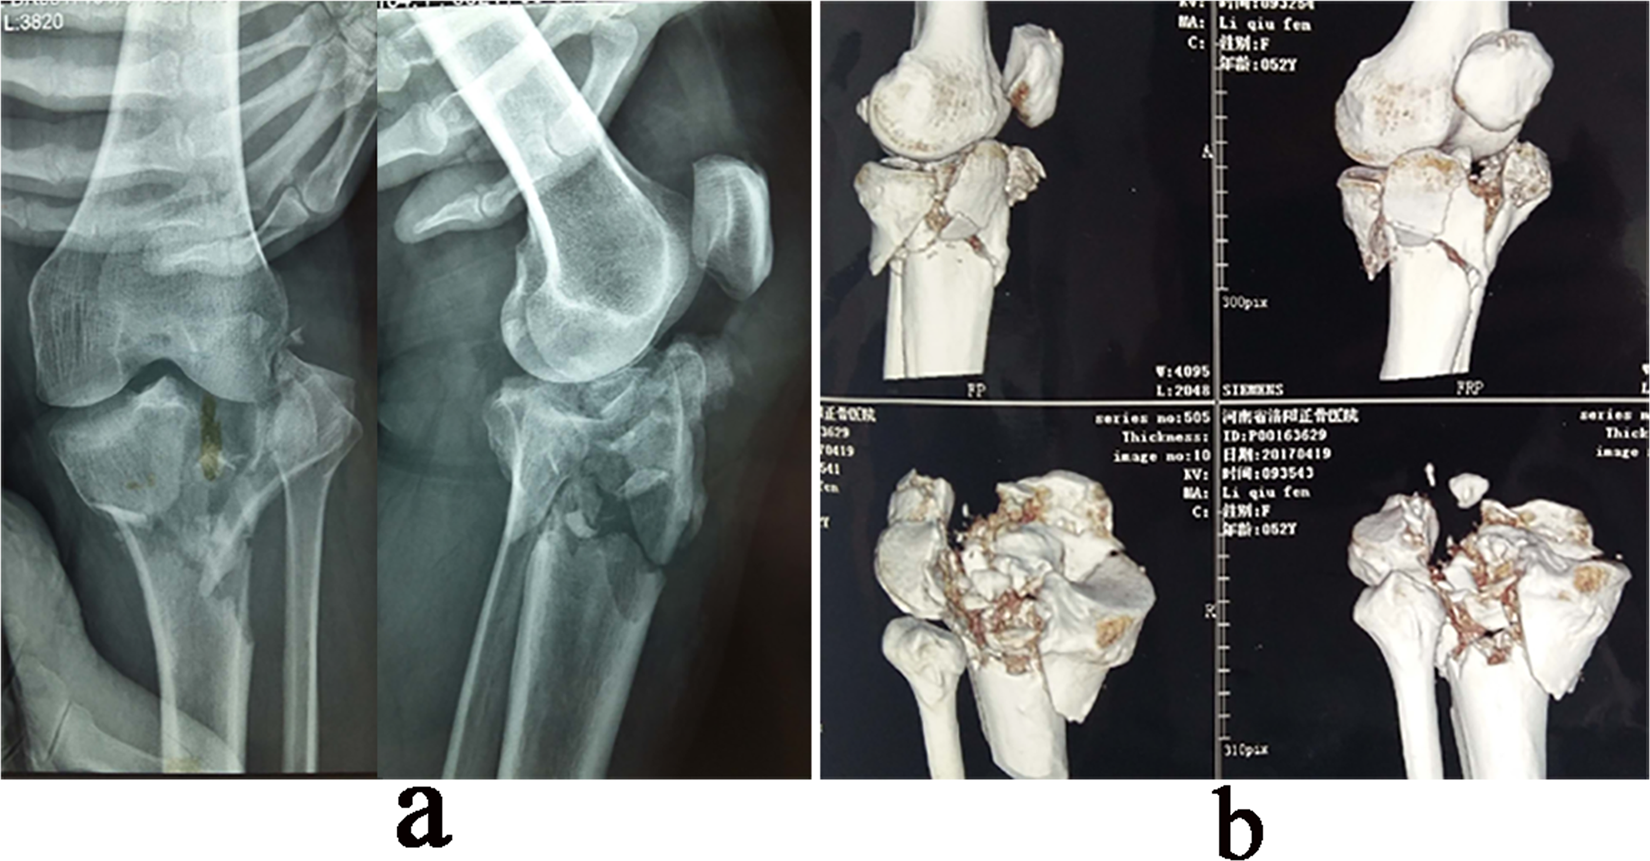

Figure 2

A 45-year-old female patient with an old and complex tibial plateau fracture. (a) Preoperative X-ray film showing the left tibial comminuted fracture (Schatzker type V). (b) Three-dimensional CT images of the fracture showing a complex tibial plateau fracture.